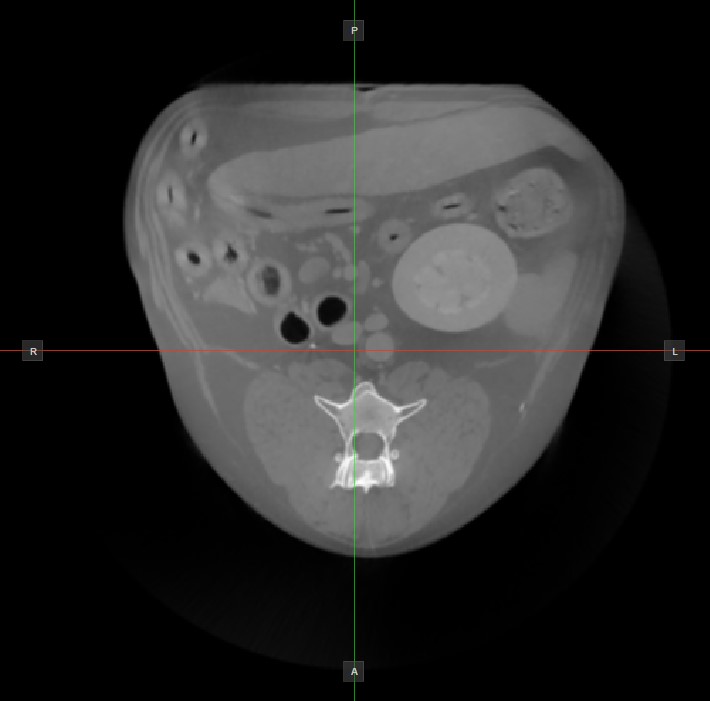

Die Position und der Schnitt der beiden anderen Bildebenen, die im aktiven Viewport nicht dargestellt werden, wird durch zwei vertikale und horizontale Linien angezeigt, die als Slicer bezeichnet werden. Die Endpunkte jedes Slicers sind mit einem Buchstaben gekennzeichnet, der der entsprechenden Richtung/Seite des 3D-Volumens entspricht, basierend auf dem RAS-Koordinatensystem.

Auf jedem 2D-Viewport werden nur vier der verfügbaren sechs Seiten angezeigt. Die Beschriftungen und die entsprechenden Seiten sind wie folgt:

Patient rechts (R), zeigt die rechte Körperseite an

Patient links (L), zeigt die linke Körperseite an

Anterior (A), zeigt die Vorderseite des Körpers an

Posterior (P), zeigt die Rückseite des Körpers an

Superior (S), zeigt die Oberseite des Körpers an

Inferior (I), zeigt die Unterseite des Körpers an